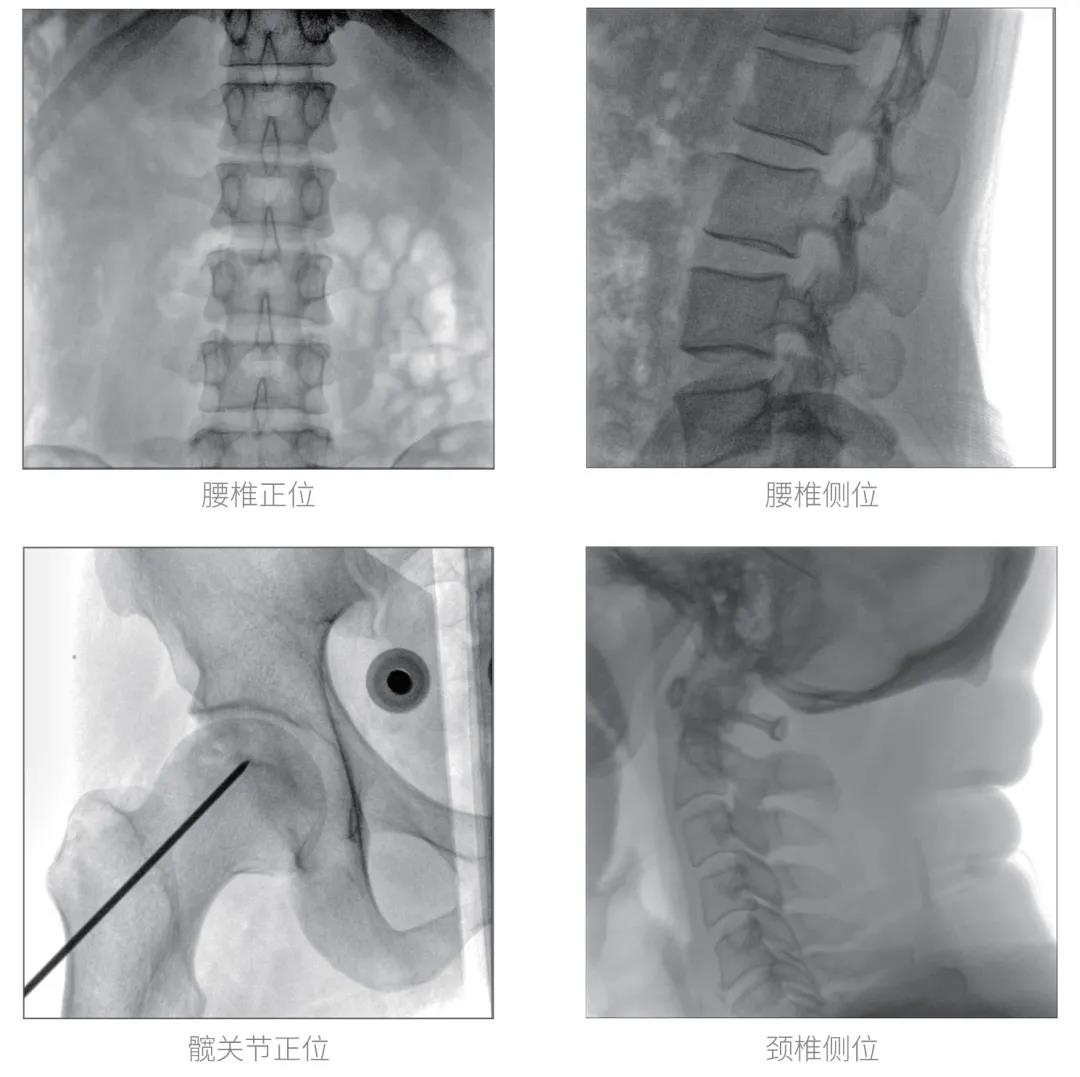

經(jīng)過認(rèn)真詳盡的設(shè)備審核驗收,“慧瞳”正式投入使用,普愛醫(yī)療一體化平板C形臂采取的動態(tài)平板探測器和智能圖像處理技術(shù),讓臨床圖像更加清晰。

普愛醫(yī)療一體化平板C形臂“慧瞳”采用小巧緊湊的一體化機(jī)架設(shè)計,配合高性能的動態(tài)平板探測器,移動靈活,成像清晰,是各級醫(yī)院開展骨科及其相關(guān)外科手術(shù)的科室使用的理想設(shè)備。

智能化實時圖像處理技術(shù),自動分析圖像并進(jìn)行增強(qiáng)處理,減少臨床應(yīng)用中處理圖像時的繁瑣操作,快速提供優(yōu)質(zhì)圖像方便完成臨床工作。

根據(jù)人體部位與射線劑量自動調(diào)整圖像幀頻,在保證圖像質(zhì)量的同時降低射線劑量。